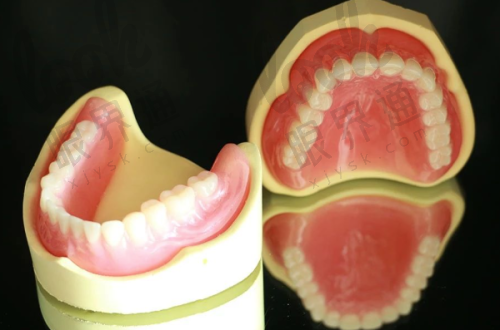

他们的医生团队也特别有意思:有从河北二院"挖"来的程新艳医生,专治各种疑难种植;还有在北京进修过的苏召医生,把活动假牙做出固定牙的舒适感。更绝的是儿童诊室,墙上画着会跳舞的牙齿精灵,MRC肌功能矫正器被孩子们当成了新玩具——难怪家长群里流传着"娃闹着要去补牙"的段子。

在全博口腔的种植中 心,医生会搬出三种"假牙根"给你选:

经济款——韩国登腾(7980元):像经济型轿车,满足基本咀嚼需求,适合预算有限人群。

经典款——瑞士ITI(1.3万):相当于牙科界的iPhone,骨结合速度快,耐用度打10年保票。

高配款——瑞典诺贝尔(1.7万):好比口腔里的劳斯莱斯,即刻负重技术能当天种牙当天啃苹果。

技术院长甄翠欣透露过个小秘密:50岁以上选韩系够用,年轻人更推荐瑞士系,因为"要用大半辈子呢"。他们还创举了"种植牙模拟器",能预测20年后牙槽骨变化,这技术全省没几家有。